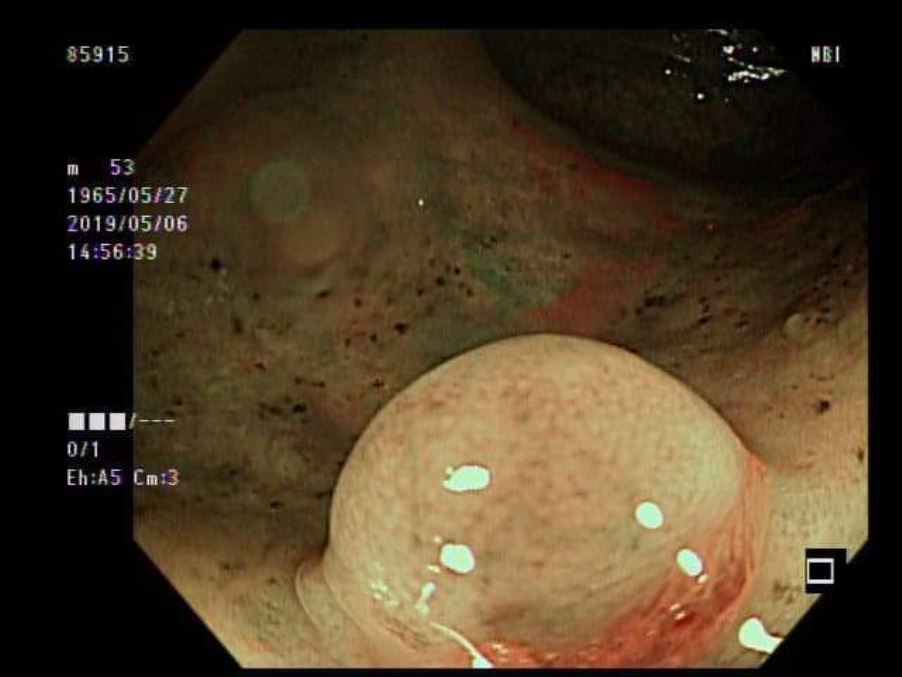

▲在胃部發現的神經內分泌腫瘤。(圖/安南醫院提供)